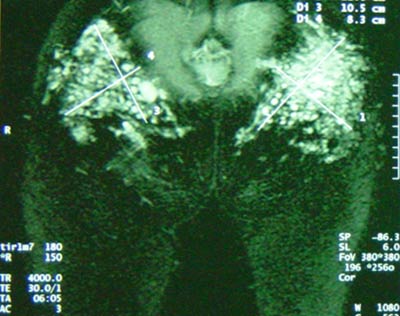

Los biopolimeros son en realidad compuestos a a base de silicona líquida a los que en ocasiones se le añaden otros materiales. Al infiltrarlos bajo la piel, el organismo los encapsula dando origen a granulomas (siliconomas) que se manifiestan como abultamientos o tumores que solo pueden extraerse mediante el bisturí (muchas veces no del todo). Pueden producir una reacción inflamatoria en el cuerpo capaz de durar días, meses o años. Los biopolímeros pueden migrar una vez infiltrados. Muchas veces los problemas con los biopolimeros aparecen años después de su utilización. A veces la silicona líquida provoca ulceras o fístulas.